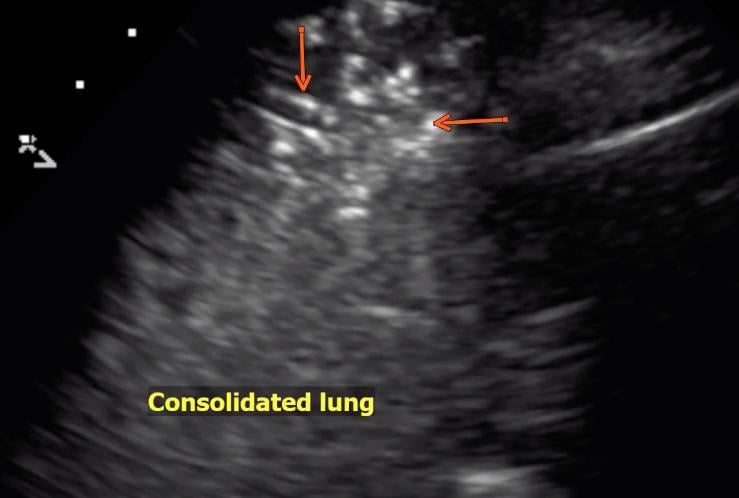

This photo gallery shows the variety of radiological presentations of COVID-19 (SARS-CoV-2) in medical imaging, including computed tomography (CT), radiograph X-rays, ultrasound, echocardiograms and magnetic resonance imaging (MRI). The radiology images show examples of typical COVID pneumonia in the lungs and the numerous complications the virus causes in the body in multiple organs, including the brain, kidneys, heart, abdomen and vascular system.